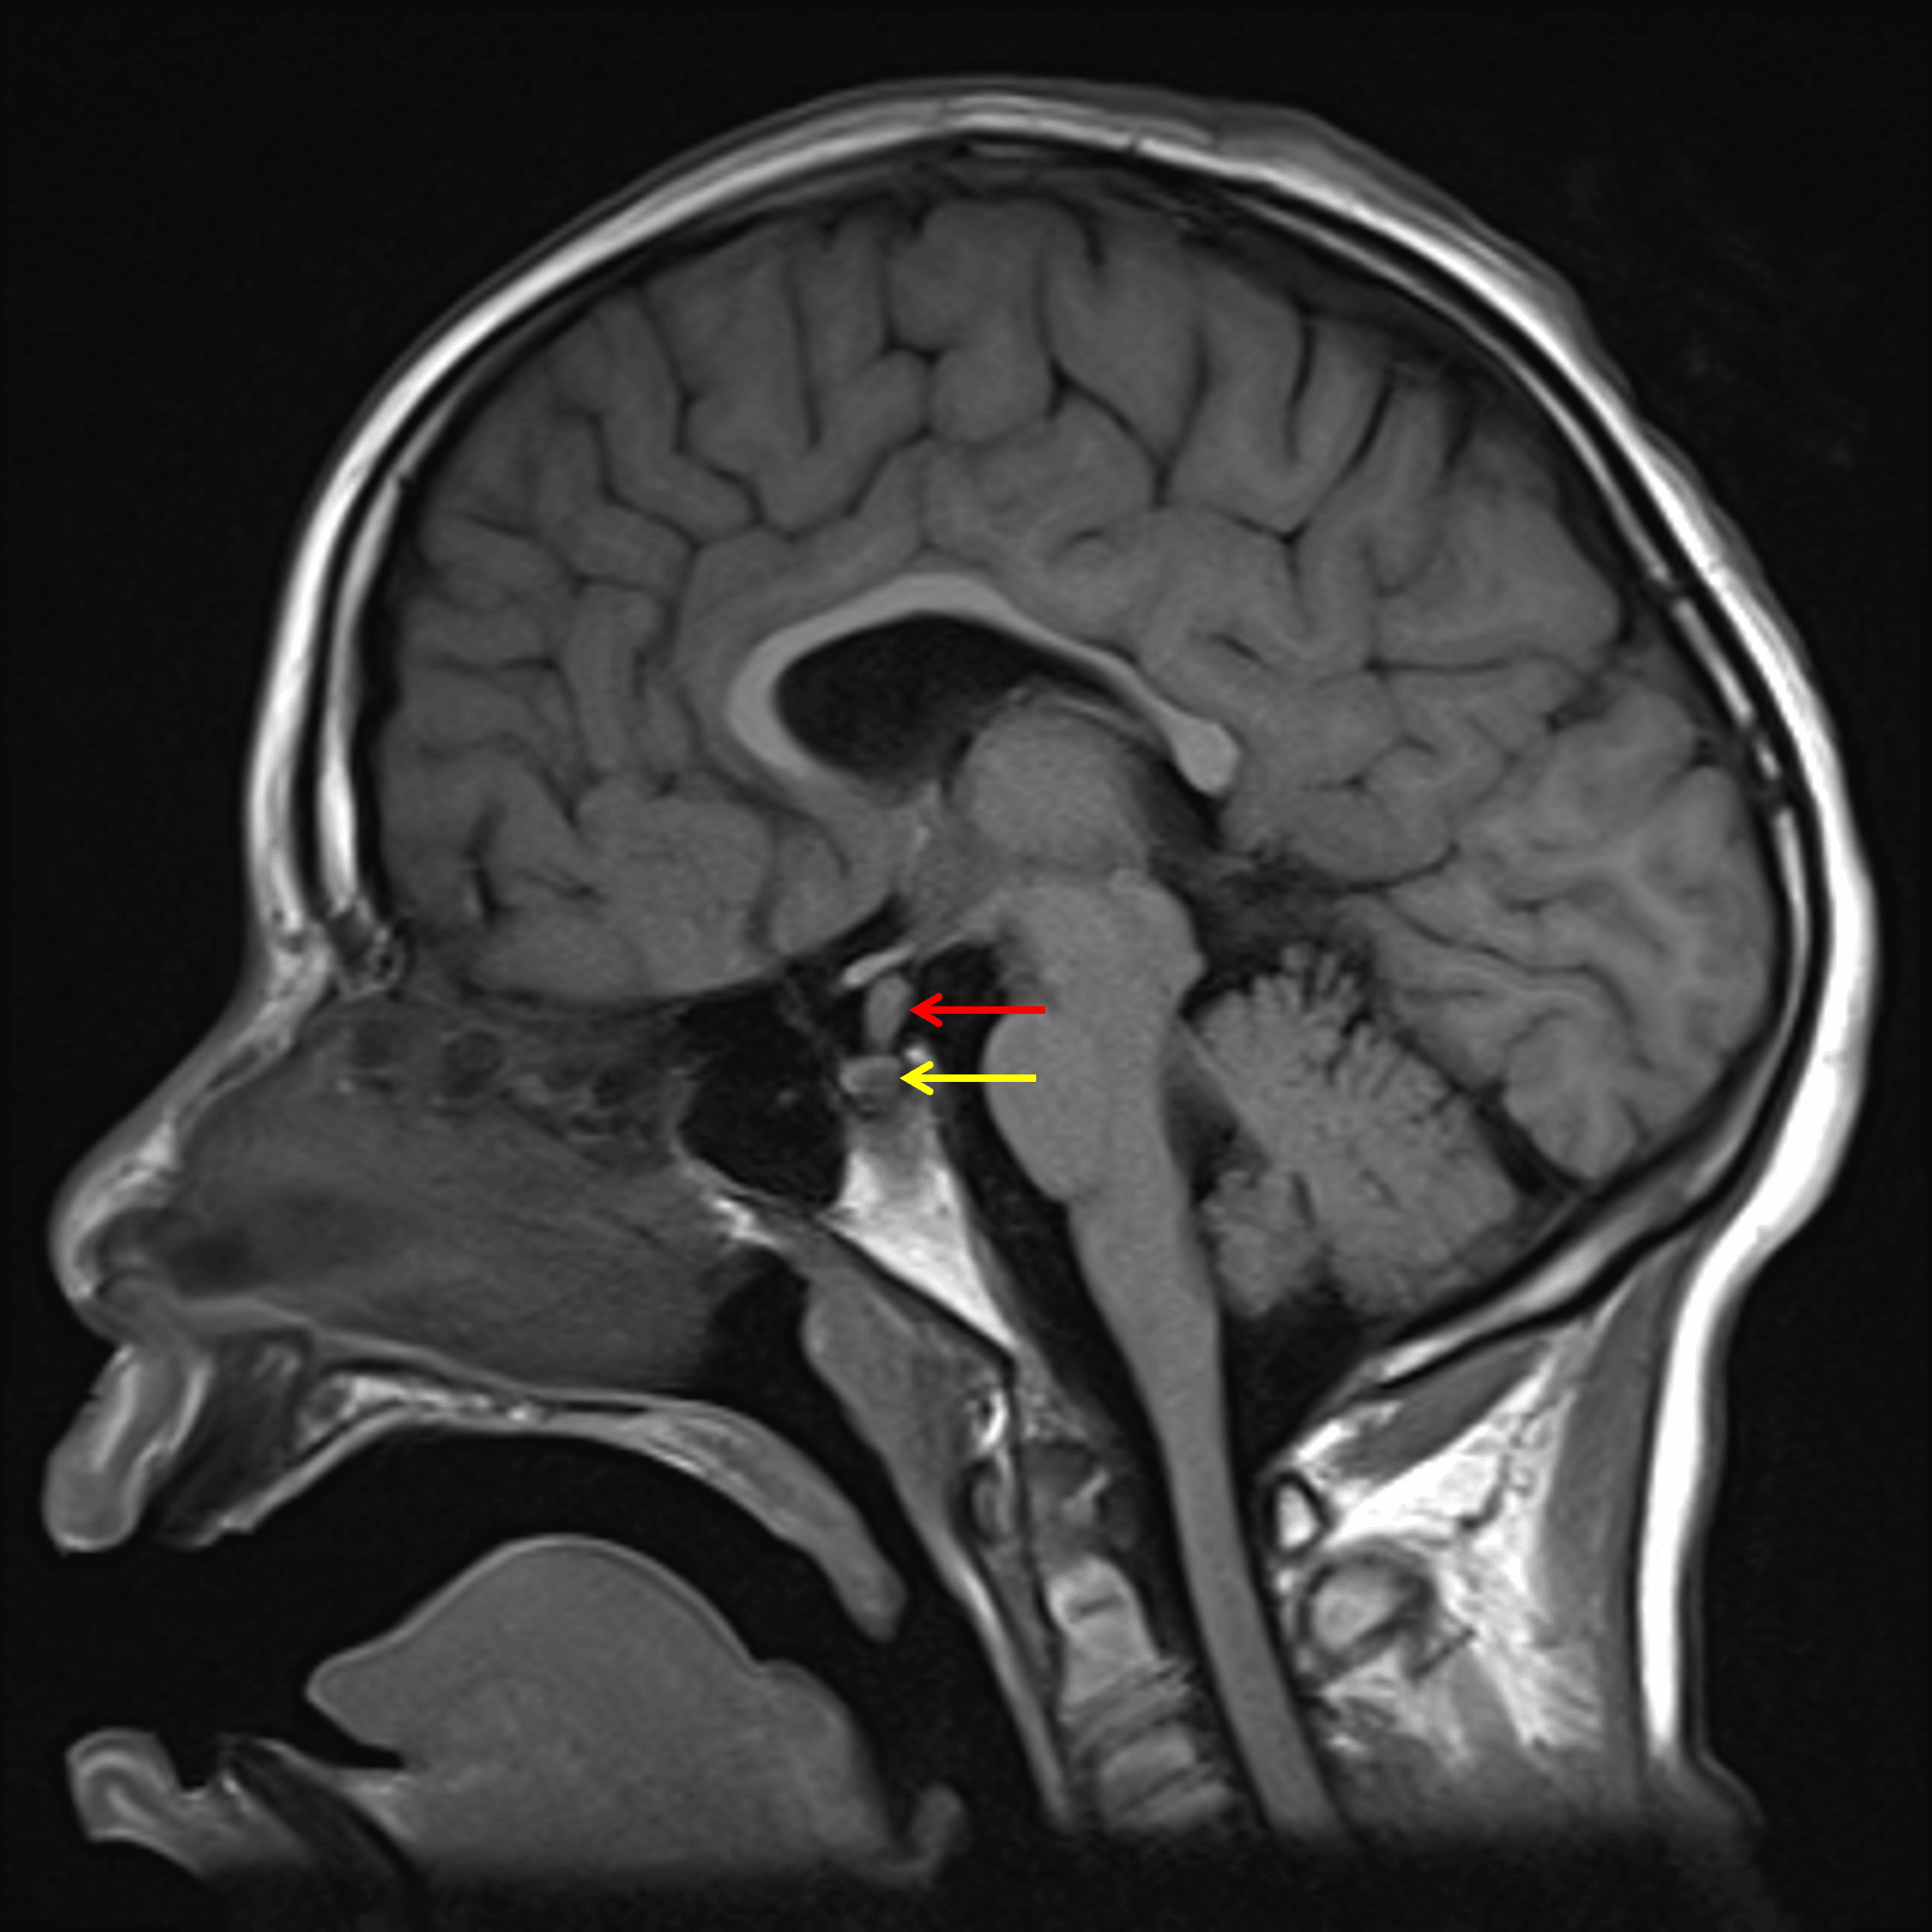

Thickening of the pituitary stalk (red arrow) with absent posterior pituitary T1 bright spot (yellow arrow).